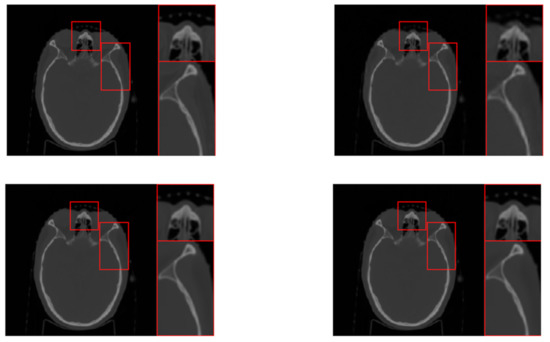

| “head1” | ||||||||||||

| SRD-DDTF | NLR-DDTF with | NLR-DDTF with | ||||||||||

| err | corr | psnr | time | err | corr | psnr | time | err | corr | psnr | time | |

| 15 | 10.50 | 99.06 | 35.81 | 470.60 | 8.97 | 99.13 | 37.16 | 860.71 | 8.10 | 99.44 | 38.03 | 1600.87 |

| 30 | 5.40 | 99.75 | 41.57 | 923.97 | 2.03 | 99.96 | 50.05 | 1251.05 | 1.93 | 99.97 | 50.50 | 1937.15 |

| 45 | 4.28 | 99.84 | 43.58 | 1367.35 | 1.28 | 99.96 | 54.05 | 1672.66 | 1.22 | 99.987 | 54.48 | 2368.40 |

| 60 | 3.80 | 99.88 | 44.61 | 1809.70 | 0.98 | 99.99 | 56.38 | 2095.44 | 0.941 | 99.992 | 56.74 | 2782.54 |